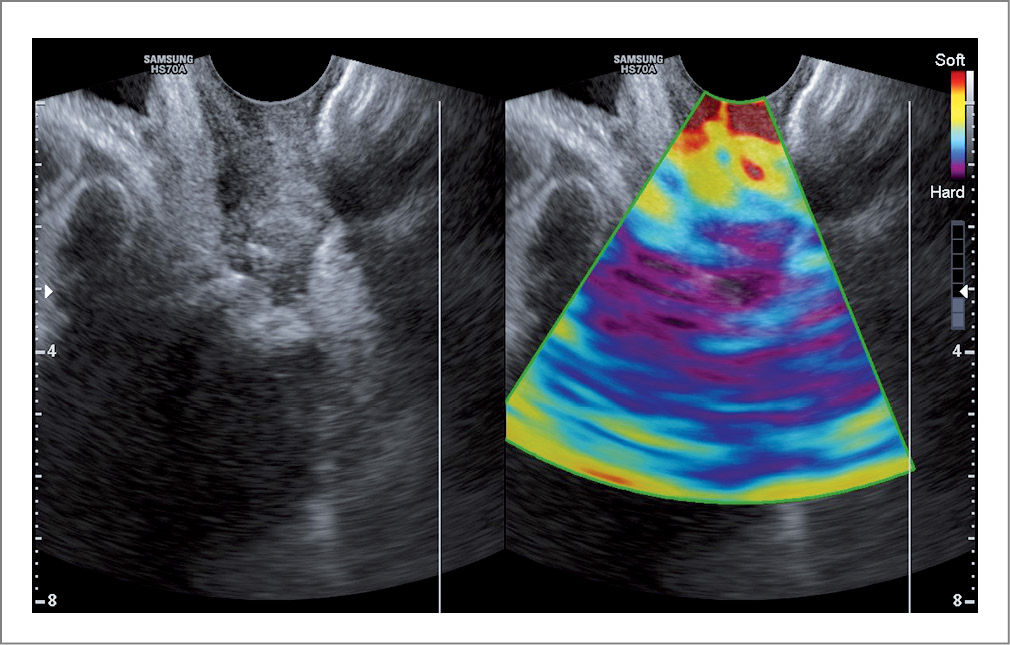

Перед оперативным лечением всем пациенткам проведено ультразвуковое исследование по технологии компрессионной эластографии, что позволило оценить эластичность ткани путем локальной деформации при дозированной компрессии. Компрессия вызывалась с помощью надавливания датчиком на стенки влагалища. Более эластичная (жесткая) ткань отображается синим цветом, ткань средней эластичности – зеленым, желто-зеленым, а более мягкая – красным цветом. Помимо качественной оценки эластичности тканей (анализа цветовой шкалы) также использовался количественный критерий – определение коэффициента деформации тканей (strain-ratio) [25].

По результатам ультразвукового исследования с эластографией во всех трех группах до операции изображение на эластограмме отображалось преимущественно красным и желто-красным цветом, что свидетельствует о более мягкой структуре ткани (рис. 2). Коэффициент деформации у данных пациенток в среднем имел значение 2,5–3,5±1,11 (табл. 2).

Рис. 2. Ультразвуковое исследование с эластографией до операции. / Fig. 2. Preoperative ultrasound with elastography.